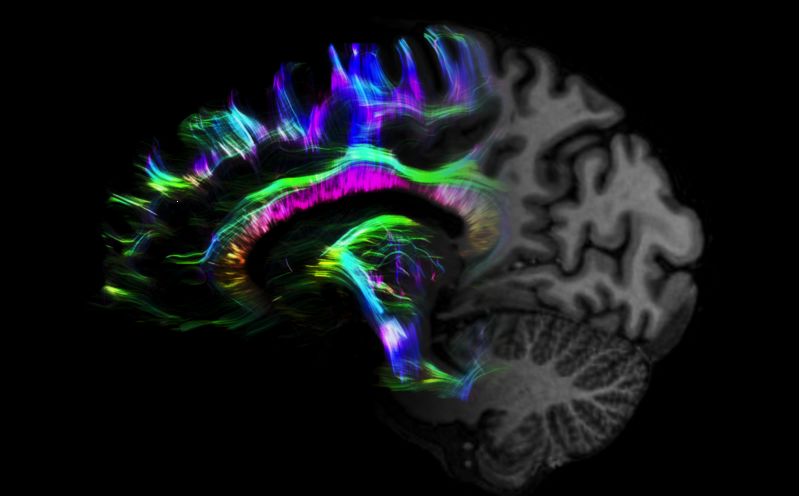

1毫米的各向同性分辨率DTI:神經(jīng)纖維束的交叉細(xì)節(jié)顯示

MAGNETOM Terra在業(yè)界首次實(shí)現(xiàn)了兩倍于傳統(tǒng)7T的超強(qiáng)梯度性能,實(shí)現(xiàn)超快速、超高效、超高分辨功能磁共振成像。如此高性能的梯度系統(tǒng)無論對(duì)于科研還是臨床都帶來了更多可能。